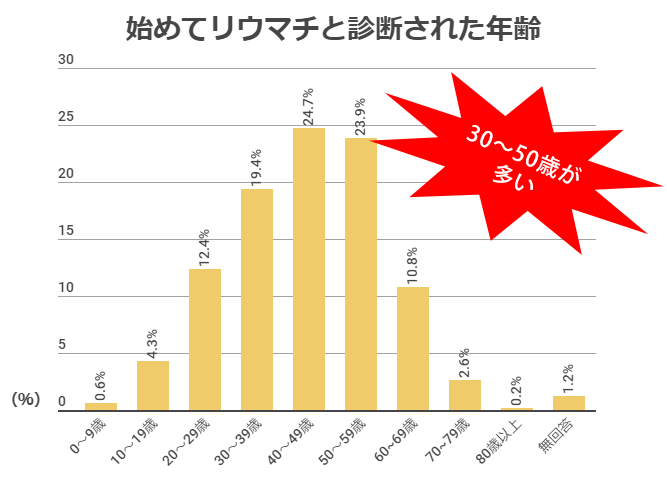

どんな人がかかりやすいの?

年代問わず発症しますが、20~50歳代の女性に多く発症する病気です。

男性も発症しますが、女性患者は男性の約5倍です。

わが国の患者数は70~80万人とされており、多くの人がリウマチのため、リウマチだからと言って心配なことはありません。